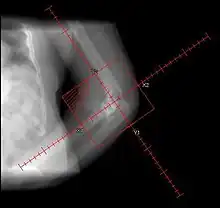

| Heterotopic ossification around the hip joint in a patient who has undergone hip arthroplasty |